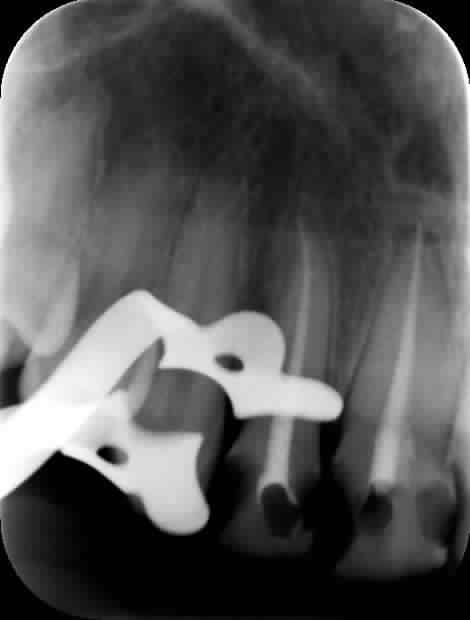

Zut, c'est la pulpo de la 47 qu'il va falloir faire.

J'ai fait sa pulpo sur la 47 aprés avoir traversé le capuchon gingival qui faisait office de composite occluso distal.

Le gars a 18 ans, une bouche bien crade, et j'ai retrouver de la plaque dentaire sur mon ecarteur photo...